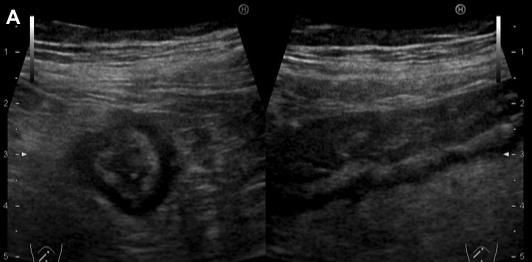

Aspect echographique percutanee d'une colite ischemique est

intra-parietale ( pneumomatose ) .

Image echographique colon descendant :

Aspect epaissisement oedemateuse hypo-echorich de la

paroi du colon

|

| |

Et image de hypo-vascularisation du colon

. |